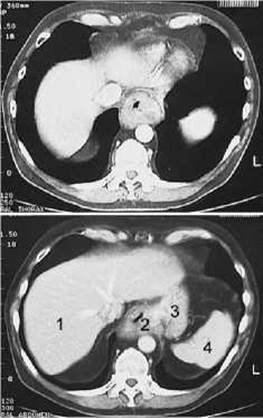

Мал. 170. Рак нижньої третини стравоходу на КТ.

1 - Печінка;

2 - потовщення стінки (пухлина) стравоходу;

3 - дно шлунка;

4 - Селезінка.

Пухлини стравоходу можуть бути доброякісними та злоякісними. Доброякісні пухлини (лейоміоми, поліпи, фіброми та ін.) зустрічаються у 10 разів рідше за злоякісні. При контрастному дослідженні стравоходу вони виявляються у вигляді дефекту наповнення з чіткими рівними контурами. Стінки стравоходу в ділянці пухлини еластичні, а складки - еластичні та типово (поздовжньо) спрямовані. На КТ, МРТ, а також УЗД із застосуванням внутрішньостравохідного датчика доброякісні пухлини виявляються у вигляді локального стовщення стінки.

Ендофітний рак інфільтрує стінку стравоходу, дифузно проростає усі шари стінки і не виступає у порожнину органа. Інфільтрована пухлиною стінка травного каналу потовщена, випрямлена, щільна, що можна виявити за допомогою КТ, МРТ, УЗД (мал. 170). Рентгенологічно виявляється звуження просвіту стравоходу з нерівними контурами, ригідність стінок, відсутність перистальтики, супрастенотичне розширення (мал. 171). Складки слизової оболонки в ділянці пухлини спочатку стають ригідними (непіддатливими, не еластичними), а пізніше перестають диференціюватись.